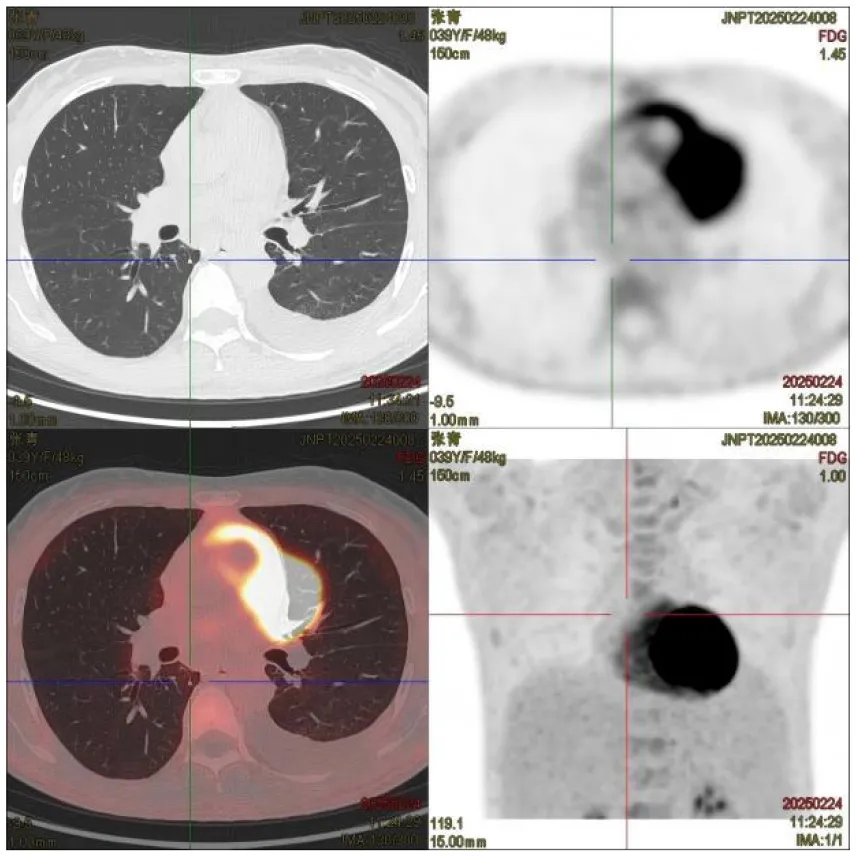

(II) PET/CT: ① Multiple enlarged lymph nodes (bilateral neck I–V, axillae, hila, mediastinum, abdomen, retroperitoneum, and iliac vessels) with mildly increased fluorodeoxyglucose (FDG) uptake and variable C-X-C chemokine receptor type 4 (CXCR4) expression; ② Splenomegaly with diffuse CXCR4 expression, normal FDG uptake; ③ Diffusely increased FDG uptake and CXCR4 expression in bones, suggesting hypercellular marrow; ④ Peritonitis, scattered ascites; ⑤ Subcutaneous edema in neck/chest/abdomen/pelvis/bilateral thighs/buttocks.

| PET/CT: | ① Multiple enlarged lymph nodes in bilateral neck I–V area, bilateral axilla, bilateral hilar region, mediastinum, abdominal cavity, retroperitoneum, and bilateral iliac vascular pathway area, mild increase in FDG metabolism, increased expression of CXCR4 to varying degrees; multiple enlarged lymph nodes ② Enlarged spleen, CXCR4 expression increased diffusely | |

| Thorax CT | Multiple enlarged lymph nodes were found in the right heart diaphragmatic angle, intra-abdomen, and retroperitoneum, which were larger than the anterior part; bone density was increased in the sternum, some vertebrae and pelvis, and bilateral femur; a small amount of fluid was found in both pleural cavities, and scattered inflammation was detected in both lungs | |

| Abdomen CT | Multiple enlarged lymph nodes were found in the right heart diaphragmatic angle, intra-abdomen, and retroperitoneum, which were larger than the anterior part; bone density was increased in the sternum, some vertebrae and pelvis, and bilateral femur; a small amount of fluid was found in both pleural cavities, and scattered inflammation was detected in both lungs. Multiple enlarged lymph nodes were found in the right heart diaphragmatic angle, intra-abdomen, and retroperitoneum, which were larger than the anterior part; bone density was increased in the sternum, some vertebrae and pelvis, and bilateral femur; a small amount of fluid was found in both pleural cavities, and scattered inflammation was detected in both lungs | |

CT images of the patient's abdomen.

A and B are abdominal CT scan images before and after autologous stem cell transplantation. A shows a significant amount of ascites, while B indicates a marked reduction in ascites. C, D, and E are PET/CT images before autologous stem cell transplantation, which show increased bone density in multiple areas, elevated FDG metabolism, no abnormal increase in CXCR4 expression; splenomegaly with diffusely increased CXCR4 expression and no abnormal FDG metabolism; and inflammatory changes in the peritoneum with scattered effusions in the abdomen and pelvis. F shows improvement after treatment.